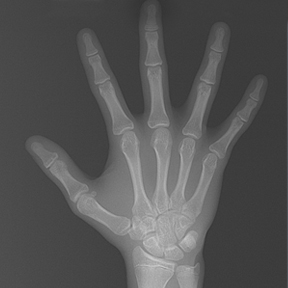

얼굴 골격의 성장에 문제가 있는지를 파악하기 위한 적절한 시기는 초등학교 입학 전인 6-7세경입니다. 이때는 유치에서 영구치로 교환되는 시기로서 부정교합 여부가 결정되는 중요한 시기이므로 이 시기를 잘 관찰하여 부정교합을 예방하는 것 또한 중요합니다. 교정의 정확한 시기는 6개월 간격으로 치과에 정기적으로 내원하여 성장 분석을 받은 후 결정하는 것이 좋습니다.